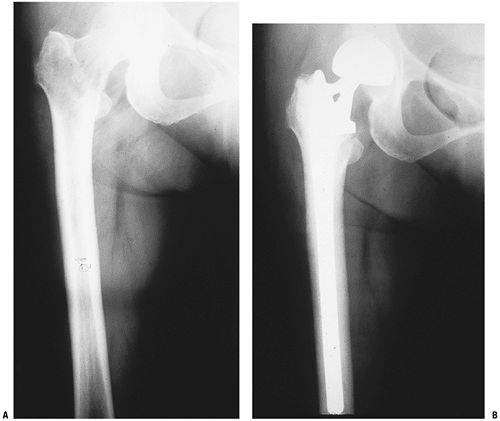

Figure 4.5-4 A woman with an impending pathologic right intertrochanteric femur fracture due to metastatic breast carcinoma (A) underwent prophylactic stabilization with a cephalomedullary locked nail (B).

Figure 4.5-5 Another patient with intertrochanteric disease felt too extensive to be amenable to stabilization (A) was treated with a calcar replacement cemented long-stem hemiarthroplasty (B).

Figure 4.5-6 Even more extensive proximal femoral metastatic destruction here (A) was treated by resection of the proximal femur with a megaprosthesis reconstruction (B,C).P.101Table 4.5-3 Surgical Options for Pathologic Fracture of The Intertrochanteric FemurSurgical Option Immediate Stability? Protects Entire Bone? Unique Potential Complications Indication Dynamic hip screw, side plate, and cement Technique-dependent; requires bone cement No Device failure if fracture nonunion Adequate proximal bone to achieve fixation Femoral reconstruction nailing Depends on bone quality, cement supplementation Yes Device failure if fracture nonunion Adequate proximal bone to achieve fixation Calcar replacement long-stem cemented hemiarthroplasty Yes If long stems are used Embolization, instability Inadequate proximal bone for fixation Proximal femoral replacement megaprosthesis hemiarthroplasty Yes If long stems used Embolization, instability Extensive destruction to below lesser trochanter